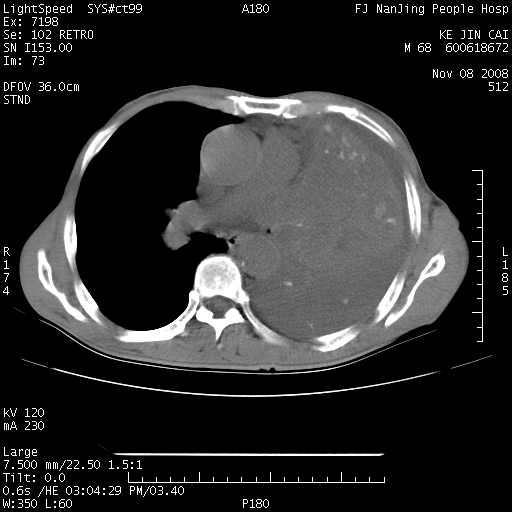

是个很有看头的病例,咋人气那么不旺?没多少人兴趣呢?这个病例几大怪:1   恶性肿瘤侵犯心肌左房怪,心肌一般不会被恶性肿瘤侵犯吧?2   左下肺均匀实变怪,内无含气,有别一般不张实变,含气肺泡完全为液体取代,而非一般不张实变的肺萎陷,冷不丁还以为是肿大的脾脏3   肿瘤本身怪,像tb肺不张4   这么有看头的病例没人气怪。呵呵。

左肺恶性肿瘤侵犯肺动脉,左心房内瘤栓,胸膜转移。